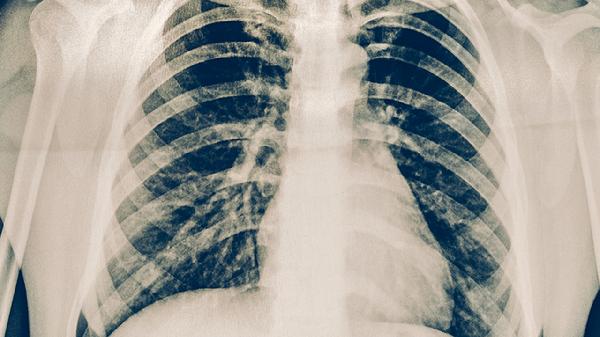

肺炎康复后需要按照医生建议定期进行胸部X线检查,确保肺部炎症完全吸收。复查时可以评估肺功能恢复情况,及时调整康复方案。定期监测体温和呼吸状况,发现异常及时就医。复查内容包括血常规检查,观察白细胞等指标是否正常。通过定期复查可以预防并发症的发生,确保彻底康复。